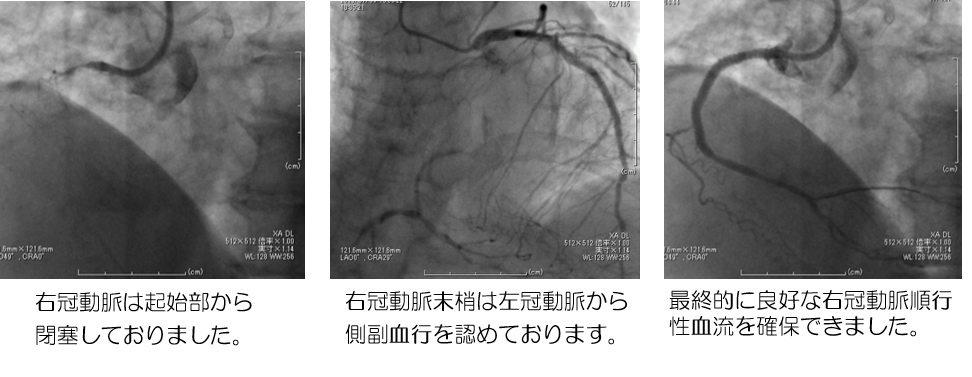

◯PCI歴のある透析中の女性

透析中の血圧低下あり精査したところ13年前に留置したステント部位の慢性冠動脈閉塞となっており、心筋シンチグラフィーにて誘発虚血を認めたため慢性冠動脈閉塞に対してPCIを施行。